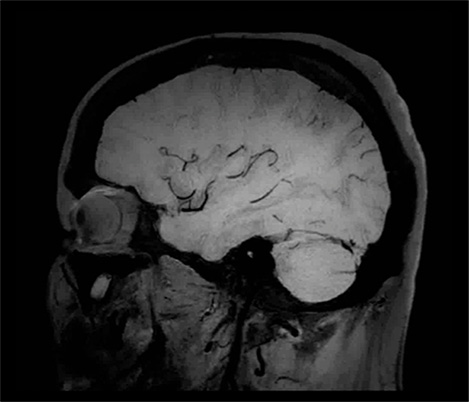

70% of radiologists consider neuro indications to be challenging, mostly due to a lack of appropriate imaging and visualization techniques¹. Philips aims to provide the best possible diagnostic clarity and treatment guidance for all patients with neurological disorders.

By leveraging our dStream digital platform, this year, we are introducing, a set of novel imaging and visualization strategies. These may empower you to resolve complex neuro questions with more certainty, as well as unlock new neuro territories in advanced Neurofunctional applications. This is a key step towards elevating neuro diagnostics and ultimately touching more lives with MR imaging.

New neuro applications

Take a look at our other neuro applications